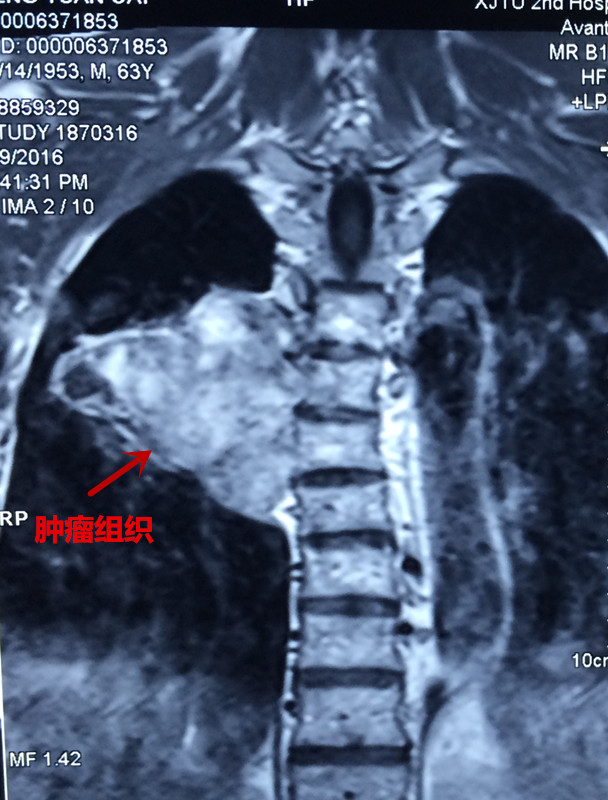

患者彭某,男,63岁,以胸背部疼痛5年,双下肢无力麻木半年之主诉入院,5年前无明显原因出现胸背部疼痛,影响夜休,就诊于当地医院,给与对症治疗,效果欠佳,背痛逐渐加重,长期服用非甾体类止痛药止痛,半年前无明显原因出现双下肢麻木、无力,走路不稳,进行性加重,未做治疗,2016年3月初就诊于当地医院,行胸椎MRI:胸6椎体水平椎管内外实质性暂未并胸6椎体附件、右侧第6肋骨骨质破坏,考虑恶性肿瘤可能,全身骨显像提示胸6椎体及右侧第6肋骨代谢异常活跃,恶性病变可能性大。当地医院拒绝治疗,为求进一步诊治,来我院门诊以“脊柱肿瘤”之诊断收入院。发病来食纳差,睡眠可,大小便正常,体重无明显变化。专科情况:脊柱生理弧度可,胸6棘突及附件压痛叩击痛阳性,半双下肢抽痛,双下肢肌张力可,肌力约3级,平乳头以下肢体感觉减退,无汗,双侧膝腱反射及跟腱反射阴性,双侧巴氏征阴性,左侧踝阵挛阳性。

患者入院后,王栋副主任,李锋涛主治医师高度重视,仔细询问患者病情,进行专科查体,分析以往患者的影像学资料,由于肿瘤组织生长巨大,严重压迫右肺,并且已经破坏了胸6椎体及其附件、右侧第6肋骨等,局部结构复杂,为了帮助手术方案的设计,我们采用3D打印技术,术前将肿瘤局部解剖结构打印成3D模型。邀请胸外科张维教授多次会诊,根据3D打印模型制定了详细的手术计划及围手术期治疗方案。经过严密的手术前准备,以王栋副主任、张维教授为主刀、李锋涛主治医师为助手,吴刚副主任医师、罗斌医师为麻醉医师,殷敏、马霞为配合护士,黄亚娟、王芳医师为术中诱发电位监护医师的手术团队努力下,手术顺利完成,成功切除了胸腔内、椎体旁及椎管内肿瘤组织,并进行了脊柱的重建。术后患者恢复良好,很快下肢感觉、肌力恢复,现患者正在康复中。

由于脊柱具有特殊的解剖结构,前方紧邻大血管及内脏,两侧有神经根走行,椎管内是脊髓,这就使得脊柱肿瘤的完整切除变得十分复杂,并且脊柱肿瘤复发后再次手术切除的机会很小,因此脊柱肿瘤手术难度大,复发率高,疗效差,一直是骨肿瘤治疗中的难点。近年来,骨二科先后开展了各种类型的原发性及转移性脊柱肿瘤的手术治疗,尤其是对于单个椎体肿瘤的整体切除,明显减少了术后的复发率,提高了患者的生存时间。对于复杂的脊柱肿瘤,由于局部解剖结构紊乱,使得手术切除变得十分困难,因此我们结合最新的3D打印技术,在术前诊断肿瘤局部进行3D打印,制成模型,在术前根据具体模型设计最佳手术方案及切除范围,术中参考3D模型提高具体操作效率,避免血管神经损伤,明显减少了手术时间及术后并发症,获得了良好的治疗效果。